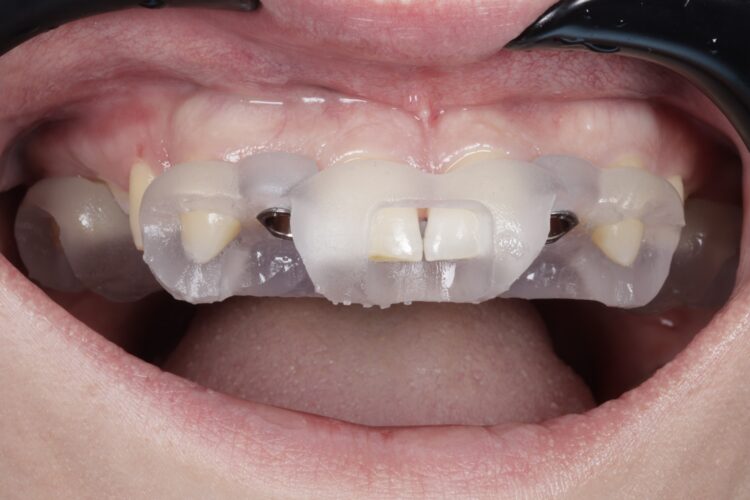

On the day of surgery, a split-thickness envelope flap was raised. Two CONELOG® Progressive-Line implants were placed through the surgical guide in the pre-determined lateral incisor positions. Soft tissue augmentation was performed simultaneously with the implant placement, and the site was sutured and closed without tension. The implants were immediately loaded using provisional crowns that were pre-fabricated in the lab.